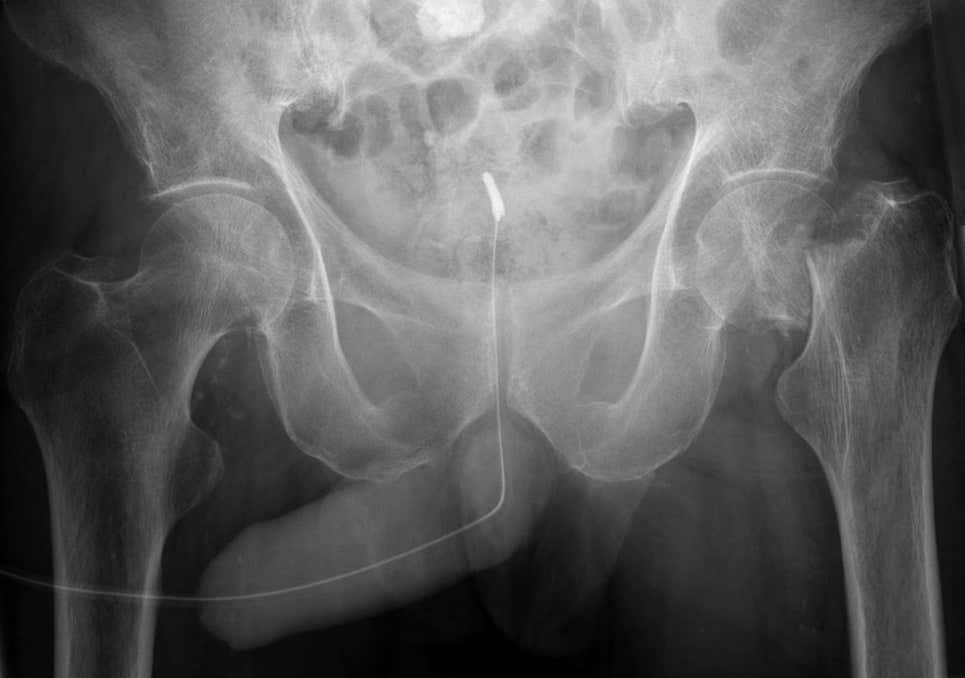

Esta es la posición sexual más peligrosa según la ciencia y es la causa del 50 por ciento de las fracturas de pene. Si hay algún empuje errático o si los movimientos de las dos partes no están sincronizados, podría provocar que el hombre se salga y sea aplastado por el hueso púbico femenino. Hablo de la posición “vaquera inversa” y el resultado de todos esos penes rotos.

Si se produce practicando sexo en relaciones heterosexuales, la posición más común para sufrir la lesión ocurre cuando la pareja está encima, ya que el hombre renuncia al control de los movimientos y, al hacerlo, el pene es susceptible de “escapar” y recibir un impacto no deseado.

Nuestra hipótesis es que cuando la mujer está arriba suele controlar el movimiento con todo su peso corporal aterrizando en el pene erecto, no pudiendo interrumpirlo cuando el pene sufre una penetración en sentido contrario, pues el daño suele ser menor en la mujer, pero importante en el pene. Por el contrario, cuando el hombre está controlando el movimiento, tiene más posibilidades de detener la energía de penetración en respuesta al dolor relacionado con el daño del pene, minimizándolo.